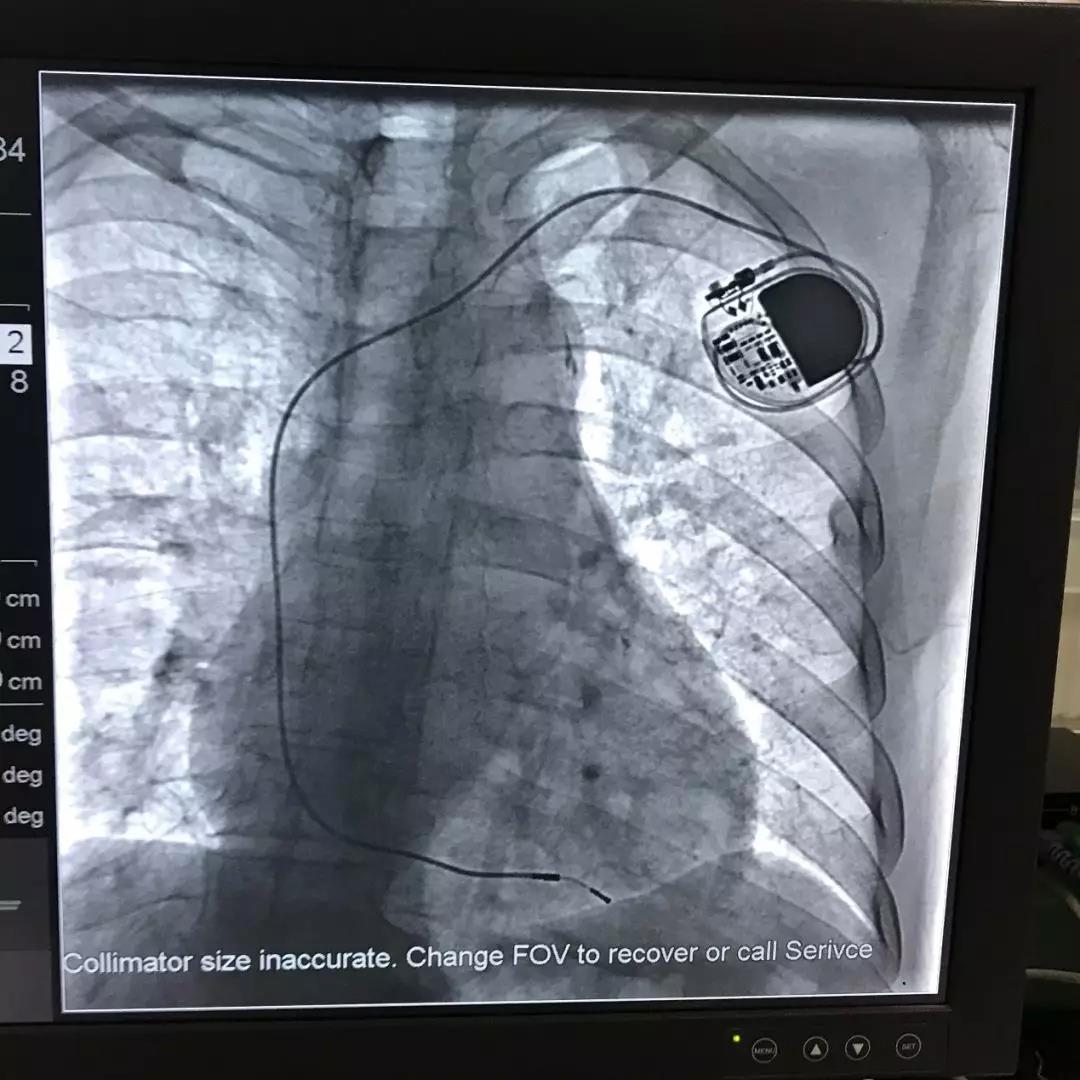

周新福主任为患者植入起搏器

起搏器植入影像